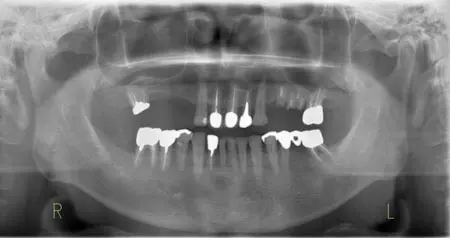

2024.12.1540代男性 天然歯をできる限り残すためにインプラントを用いながら虫歯の治療と噛み合わせを改善した症例

インプラント

2024.12.1560代男性 痛みのあるブリッジを除去してインプラントブリッジを併用し噛み合わせを改善した症例